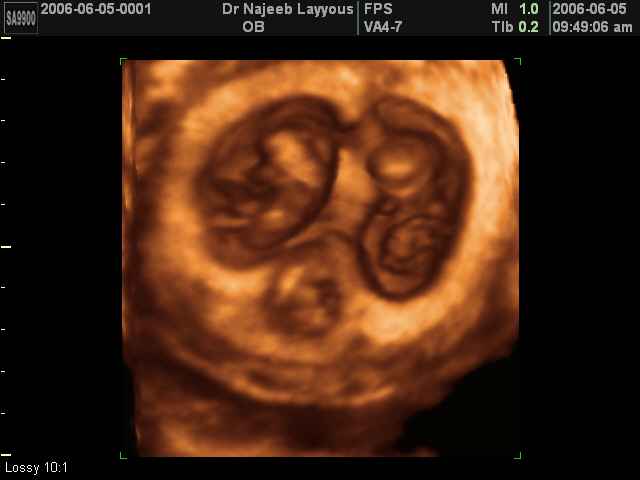

- صور لتوائم

صور لتوائم بجهاز الالتراساوند ثلاثي الأبعاد | الدكتور نجيب ليوس